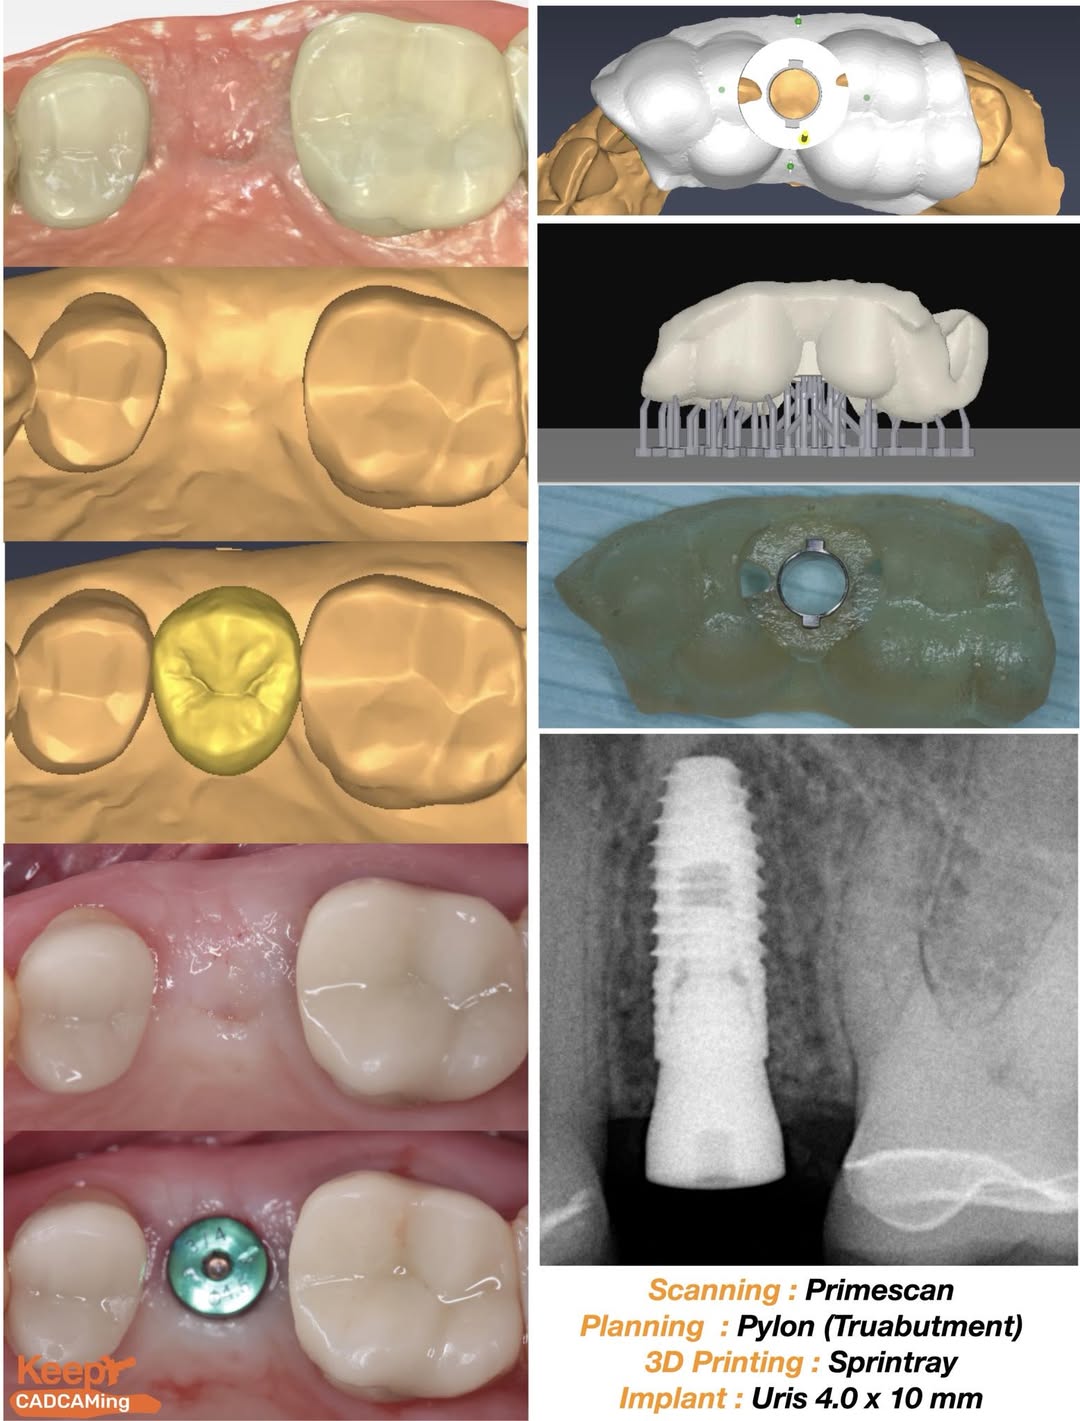

Single Implant Placement is a crucial skill for general dentists. My experience improved significantly when I began using guided techniques. This approach boosts confidence, enabling more cases and fewer referrals by allowing advance planning and visualization. Developing a workflow for in-house guide fabrication and using a seamless kit is essential for a smooth process.

Here is my 4 step process for guided surgery :

Step 1 : Take intra oral scans and CBCT ( Taken by assistants )

Step 2: Import them into Pylon ( Free planning software from Truabutment ) and plan the placement myself. (10 -12 min)

Step 3 : Export the STL for the guide and 3D print it with SprintRay. ( Done by assistants )

Step 4: Guided surgery with Uris implants ( 10 min )